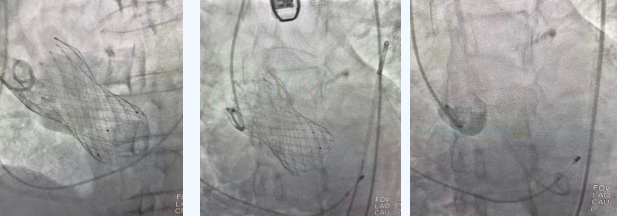

在麻醉手術(shù)中心的配合下,曾廣偉主任用導(dǎo)管經(jīng)股動(dòng)脈鞘進(jìn)入主動(dòng)脈瓣目標(biāo)位置,經(jīng)豬尾導(dǎo)管造影可見主動(dòng)脈瓣大量返流,因左室流出道較寬,大于瓣膜落腳點(diǎn)直徑,瓣膜釋放位置選擇及釋放難度極大。更為關(guān)鍵的是,患者常規(guī)四個(gè)錨定點(diǎn)只有一個(gè)可以用,定位要極其精準(zhǔn)才能保證瓣膜釋放后牢靠,同時(shí)不能有大的殘余瘺!稍有移位可能就需要再次植入瓣中瓣或者開刀!

術(shù)中,曾廣偉主任團(tuán)隊(duì)高效配合,完成了特定時(shí)間點(diǎn)起搏心臟、臨時(shí)短時(shí)間關(guān)閉呼吸機(jī)、降低主動(dòng)脈瓣阻力、快速釋放瓣膜等一系列高難度操作,有效保證瓣膜精準(zhǔn)釋放。瓣膜釋放經(jīng)TEE確認(rèn),主動(dòng)脈瓣膜釋放位置佳,經(jīng)豬尾導(dǎo)管造影,主動(dòng)脈瓣返流即刻消失,且無(wú)瓣周瘺。